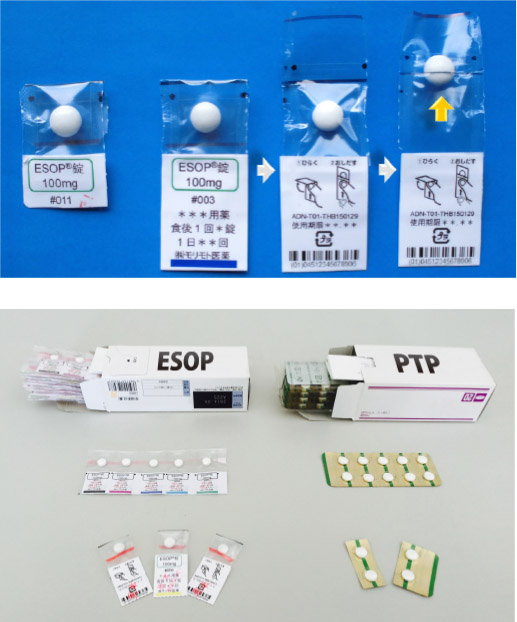

Http Www Morimoto Iyaku Jp Wp Content Img Sympo Downloadpage Esop Shoukai 151221 Pdf

Http Www Morimoto Iyaku Jp Wp Content Img Sympo Downloadpage Esop Shoukai 151221 Pdf